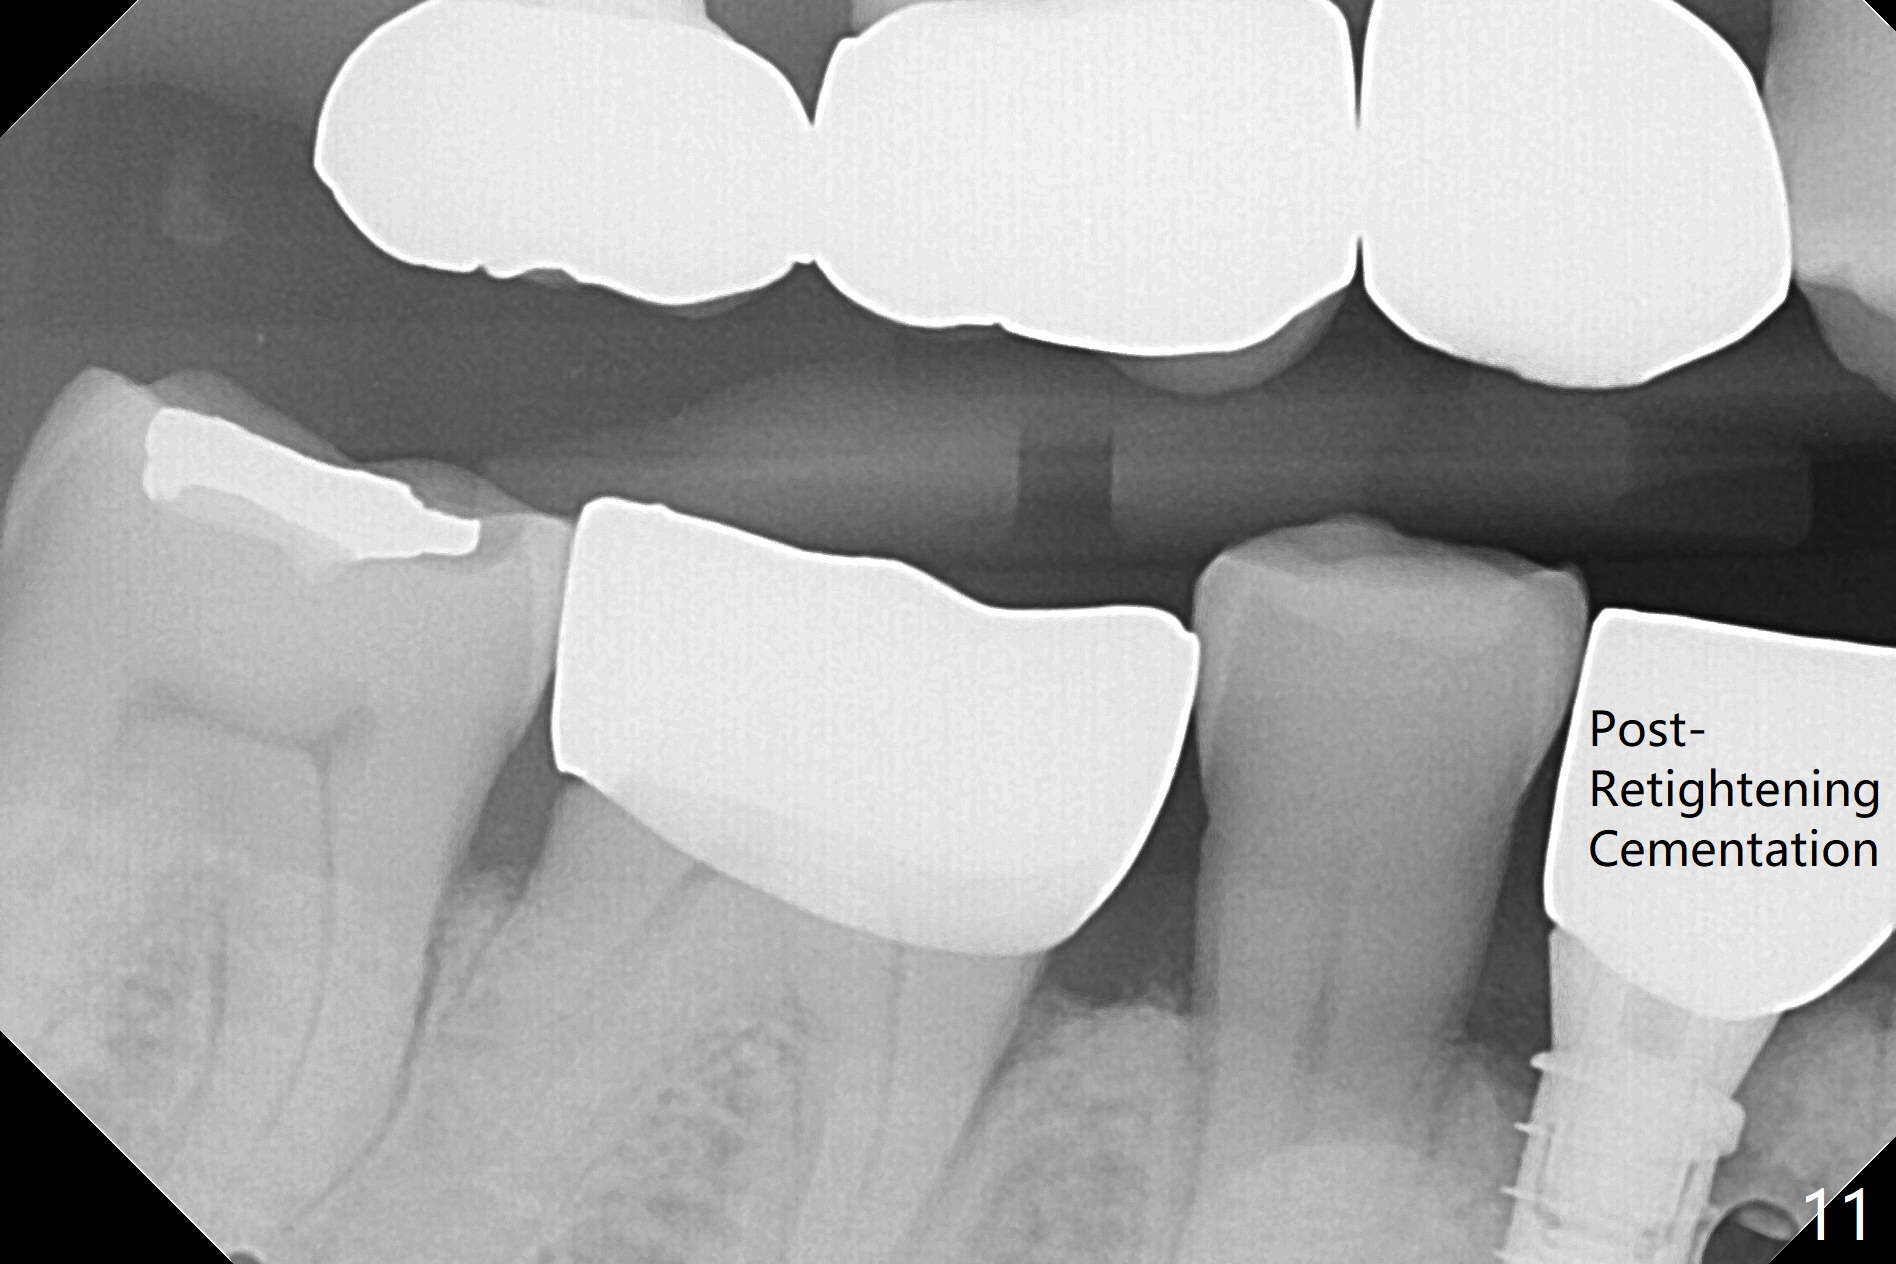

In fact the mesiodistal space of the site of #28 is within normal limit. The buccal plate atrophy is striking (Fig.1) with a fistula (^, associated with underlying residual root tip). When the flaps are raised, the ridge is triangular with the lingual plate (Fig.2 *) higher than the buccal one. Because of the slope, the multiple-drill approach is adopted in stead of single-drill one, because the marking bur is wobbling after 1.6 mm osteotomy at 13 mm (Fig.3). After placement of a 4x11 mm implant, a 4.5x4(2) mm abutment is inserted (Fig.4). The abutment and the implant act as a mesh (framework) so that bone graft and collagen membrane can be laid upon them buccolingually. When the flaps are sutured, there is less tension than that without the abutment. Furthermore, the buccal tissue volume seems to be increased (Fig.5 (<: fistula, which should heal soon), as compared to Fig.1). Tale photos to show effectiveness of the simultaneous GBR and disappearance of the fistula. Three months postop (Fig.6,7 (incomplete abutment seating)), the implant is loaded for intrusion of the opposing supraerupted tooth. The patient returns with chief complaint of food impaction between #27 and 28 three years 7 months post cementation; there is an open contact. Before pick up impression the distal convex surface of #27 is trimmed. The repaired crown has tight proximal contacts before (Fig.9,10) and after (Fig.11) retightening and cementation.